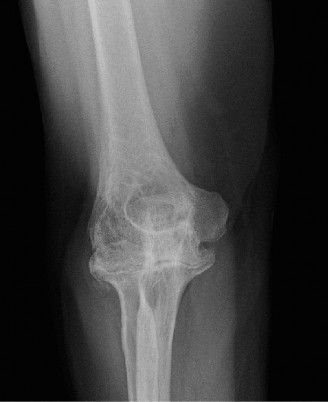

Treat a patient with infected total shoulder arthroplasty? CASE 21 A 70-year-old, right-hand-dominant female presents to clinic complaining of 4 years of gradually worsening chronic right shoulder pain and stiffness. She says the pain is worse at night and with any range of motion, denies a history of trauma, pain in other extremities, or numbness or tingling of the right upper extremity. She notes that her mother suffered from rheumatoid arthritis that affected her shoulder. Physical examination reveals decreased muscle bulk over the right supra- and infraspinatus fossae compared to the contralateral side, limited active and passive ROM, marked weakness with external rotation, and 4+/5 strength with shoulder abduction. X-rays of the right shoulder are shown in Figures 2–58 and 2–59.

The correct answer is (C). Rotator cuff tear arthropathy consists of a combination of rotator cuff insufficiency, glenohumeral joint degenerative changes, and superior humeral head migration. It is more common in women and also more often found on the dominant side. The patient’s clinical examination with weakened external

rotation and muscle atrophy signaling incompetent supra- and infraspinatus muscles point to rotator cuff insufficiency, and her plain films reveal narrowed glenohumeral joint space as well as superior migration of the humeral head. Choice D is incorrect because, while radiographs would show narrowing of the glenohumeral joint space, they would also likely show numerous osteophytes and posterior wear of the glenoid. Choice B is incorrect because, while adhesive capsulitis does present as decreased active and passive range of motion, the patient’s constellation of symptoms pointing towards rotator cuff insufficiency along with the radiographs make cuff tear arthropathy the more likely choice. Finally, Choice A is incorrect because even though she has a positive family history of rheumatoid arthritis, it is less likely to present only in a single joint. Also, rheumatoid arthritis on radiography appears more as an erosive process without the characteristic superior migration of the humeral head.

The correct answer is (A). Superior migration of the humeral head would be most indicative of chronic rotator cuff insufficiency associated with cuff tear arthropathy, as it is a direct result of the inability of the rotator cuff tendons to help maintain the humerus in its normal position. Acetabularization of the undersurface of the acromion is commonly associated with superior migration of the humeral head found in rotator cuff tear arthropathy, and can be assessed using the Hamada classification, which is based on measurements of the acromiohumeral interval on radiography (Table 2–8). Choices B and C are incorrect because, while narrowed glenohumeral joint space and subchondral sclerosis are associated with rotator cuff arthropathy on radiographs, they indicate degenerative joint changes rather than chronic rotator cuff insufficiency. Choice D is incorrect because it is not a specific sign of rotator cuff arthropathy.